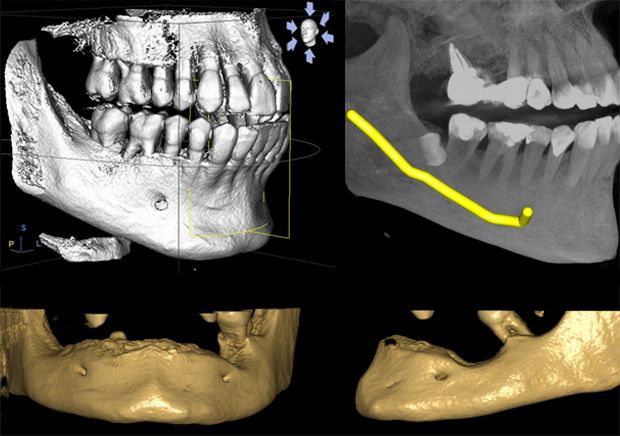

Το σύστημα CBCT οδοντιατρικής αντιπροσωπεύει την κορυφαία τεχνολογία στην τρισδιάστατη απεικόνιση. Η υπολογιστική τομογραφία γνάθου παρέχει λεπτομερείς πληροφορίες για την οστική αρχιτεκτονική, απαραίτητες για τον σχεδιασμό εμφυτευμάτων και ορθογναθικών επεμβάσεων. Το CBCT γνάθου επιτρέπει την ακριβή αξιολόγηση της οστικής πυκνότητας και των ανατομικών δομών, διασφαλίζοντας την ασφαλή και επιτυχημένη τοποθέτηση εμφυτευμάτων.

Η εξέταση CBCT συνιστάται κυρίως πριν την τοποθέτηση εμφυτευμάτων, για την αξιολόγηση πολύπλοκων ενδοδοντικών περιστατικών ή όταν χρειάζεται λεπτομερής τρισδιάστατη απεικόνιση της γνάθου.